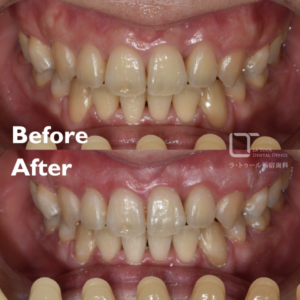

セラミック治療・40代(女性)|「歯科治療への恐怖心が強い方に静脈内鎮静下で3本同時修復」

治療内容 セラミック治療(アンレー) 施術費用 88000円×3本(別途鎮静代) 通院回数 2回 通院期間 メリット 審美性に優れており、天然歯に近い自然な色や形に仕上がります。金属を使わないため、金属アレルギーの心配がなく、高い適合精度と耐久性によって、美しさと機能を長く維持しやすくなります。 リスクと副作用 セラミック治療は保険適用外(自由診療)です。強い衝撃や過度な力が加わると、まれに割れることがあります。治療後にしみる症状がみられることがありますが、多くは時間とともに落ち着いていきます。 セラミック治療の治療例です。歯科治療に対する恐怖心が強く、 […]